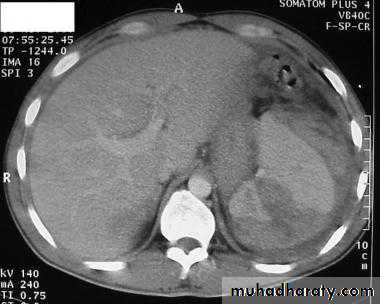

Fatty infiltration of the liver

It is a frequent finding, particularly in those with hypercholesterolaemia, obesity, diabetes or those who take alcohol to excess. It may involve the whole liver or it may just involve individual subsections

At CT, liver density is less than splenic density

At US, increased liver echogenicity (bright liver)MRI useful in problem cases because fat gives a characteristic set of signals